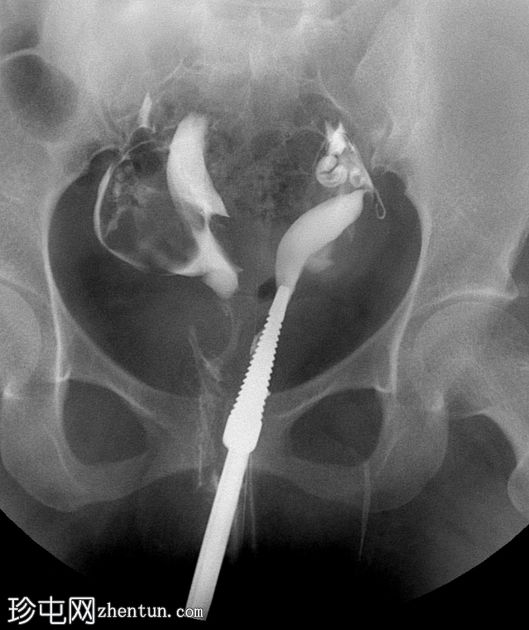

子宫输卵管造影

正位

子宫输卵管造影显示两个独立的子宫腔,完全重复。可见两条独立的宫颈管。每个子宫角分别与其对应的输卵管相通。无统一的子宫底;子宫角明显分离。两个子宫腔均充盈并溢入腹腔。

子宫输卵管造影 (HSG) 显示两个间距较大的子宫腔和两个宫颈,强烈提示双子宫。

仅凭 HSG 可能不足以确诊——通常需要进一步影像学检查(MRI/三维超声)来评估子宫外轮廓并排除其他苗勒氏管畸形。